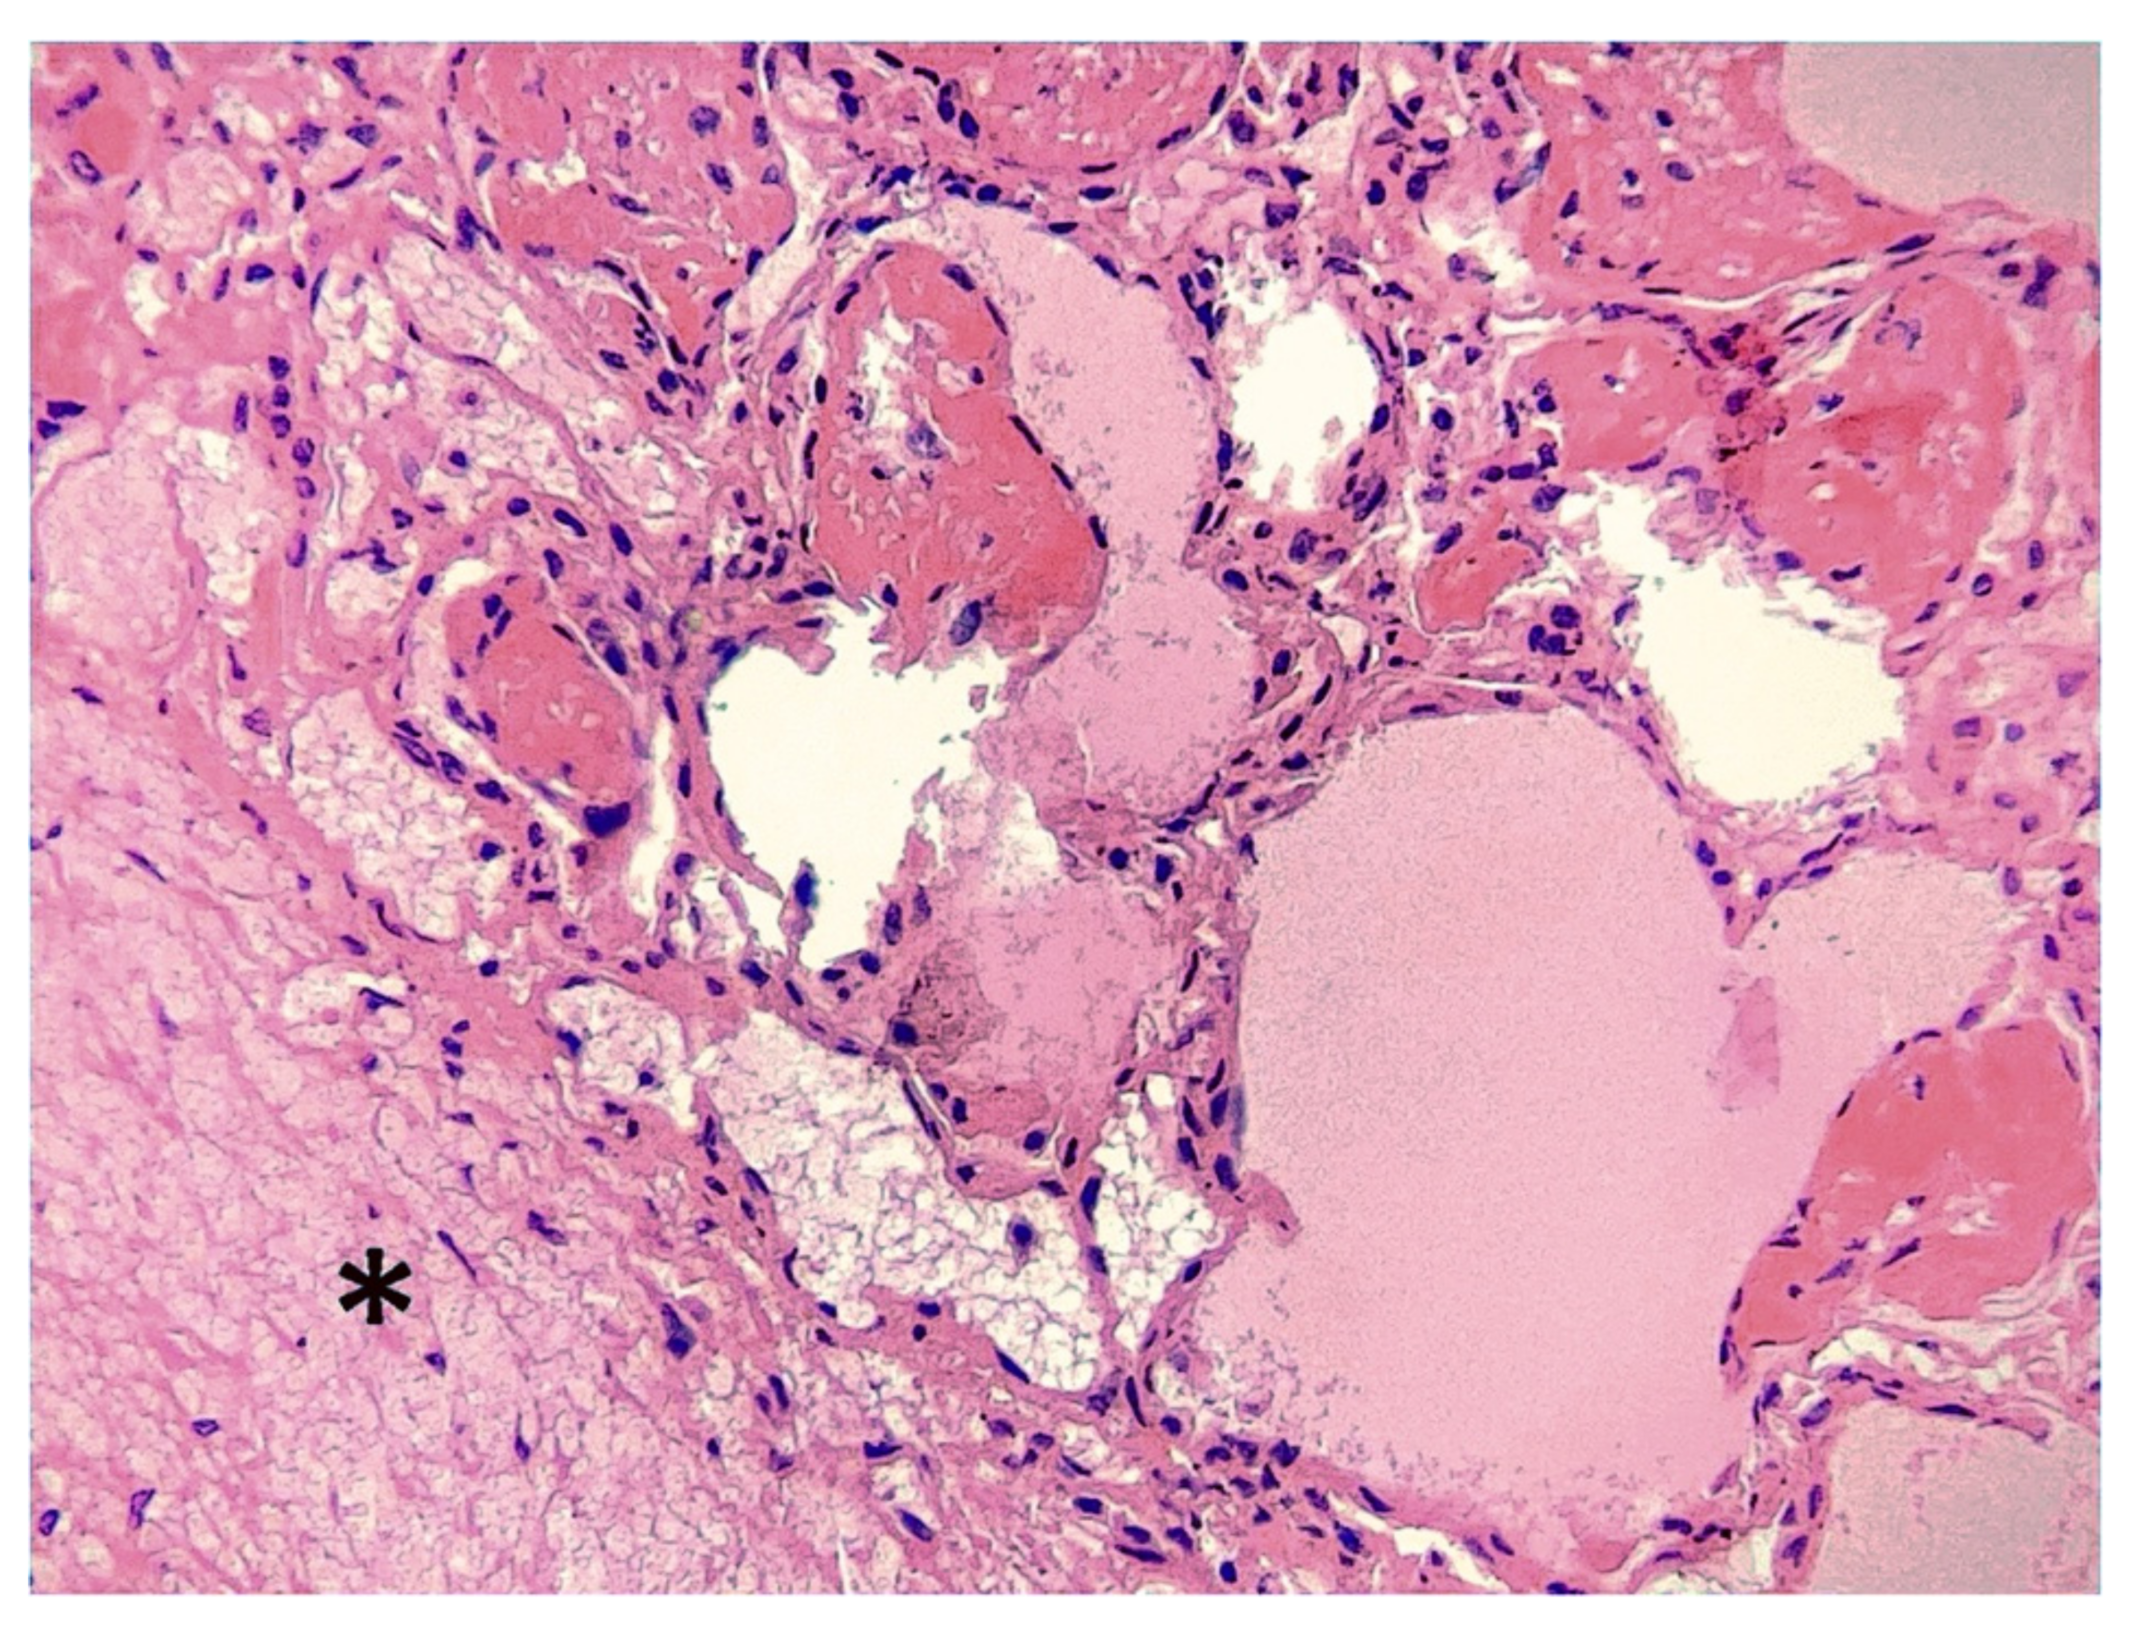

Bronchi, bronchioles, alveoli and interlobular septa appeared diffusely and severely hyperemic, necrotic and hemorrhagic. Severe edema and multifocal fibrin deposits were observed within the airways and interlobular septa (Figure 4). Although detectable, bacterial aggregates and inflammatory cell infiltration were less evident in the alveolar spaces when compared to the tracheal mucosa.

Figure 4. Lungs. Almost all alveoli are edematous or filled with fibrin. The interlobular septa (*) are thickened and embedded by abundant fibrinous exudate (HE, magnification ×200).